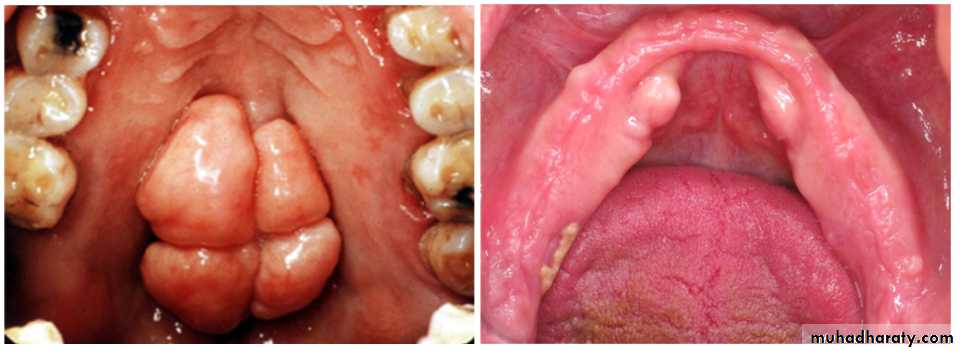

Remove or not…act as shelfRemoval of tori:

Mandibular torus:Interfere full or partially with denture

Ulceration

Interfere with speech if too large

Crestal incision……..flap reflected

osteotome……malleted if clear or bur……stent needed

Palatal torus:

Small …ignore …relief

Same as mandibular indication

incisions:

Single midline palatal incision, Y, Horse shoe

Cut with fissure bur…..then use osteotome.. stent